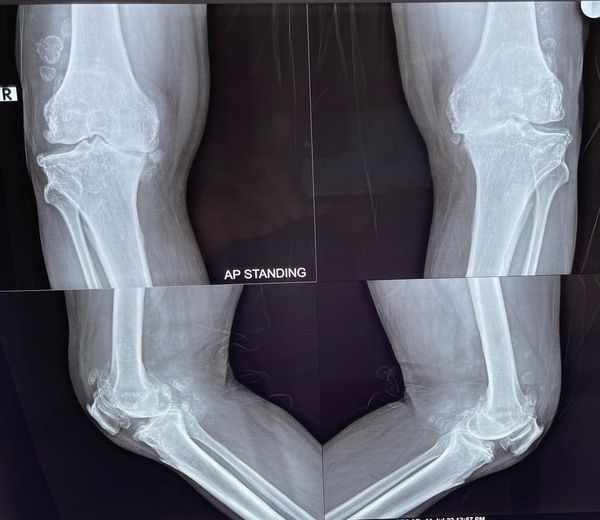

68 year old man ACL (anterior cruciate ligament) reconstruction of Knee

There used to be a common consensus that ACL reconstruction of knee should not be done in old age, this idea has now largely been debunked with statistical evidence. this 68 year old man with a traumatic anterior cruciate ligament tear had intact lateral and medial meniscus and quite normal cartilage in the weight bearing […]